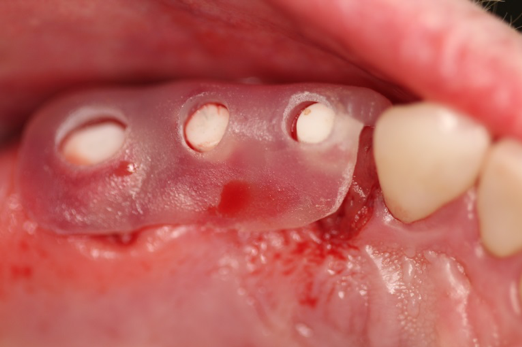

Fig 20. Immediately after extraction and placement.

Figure 20

Occasionally dentists are presented with extreme challenges with long-term restorations and replacing missing teeth. Dentists must evaluate the patient's condition, develop optimum long-term oral health, and attempt to meet the patient's expectations. Figure 18 showed a class III malocclusion with deep bite, multiple abfractions, and less-than-ideal occlusal plane, but the patient wanted to replace his maxillary right canine only. A discussion with the patient regarding occlusal disharmonies and comprehensive recommendations for full-mouth rehabilitation revealed that the patient had a limited budget for dental care. The patient understood the ramifications of his comprehensive dental needs not being affordable. Decisions were made to atraumatically remove the maxillary right canine (Figure 19) and immediately place a ceramic dental implant (Figure 20). Polytetrafluoroethylene (PTFE) 4-0 sutures were placed to help support soft tissues, and then a full-arch Essix-style retainer with a flowable composite facial veneer was used to provide some esthetics during the patient's healing phase (Figure 21). The implant and the retainer were not to be in contactthe retainer may occlude with the opposing dentition and also be passive in relation to the ceramic implant.